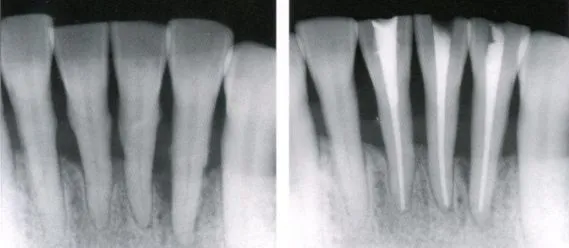

1:适应症的检查:详细询问病史,是否有自发痛,夜间痛,疼痛不能定位等症状,通过叩诊,冷热诊等方式确定患牙牙位,并通过拍X光片(术前必须)加以确认。

7:术中X片:查看根管预备情况,是否预备到根尖止点处。